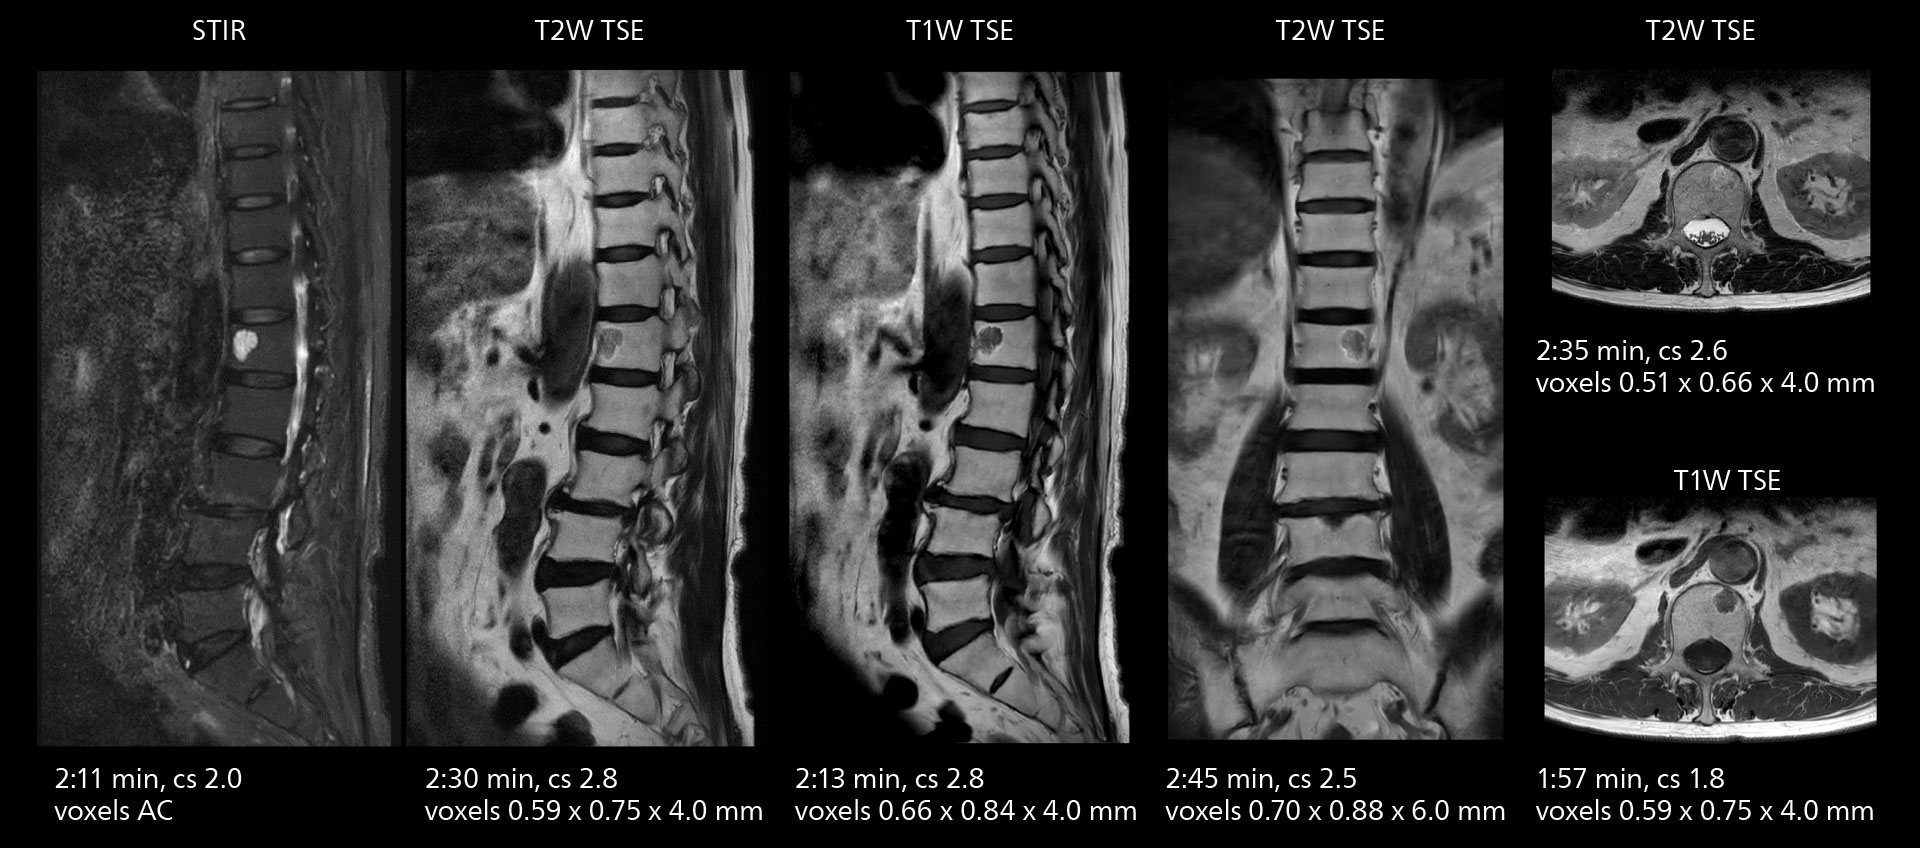

Crisp images are obtained with high resolution and short scan times using Elition X. A cyst can be seen.